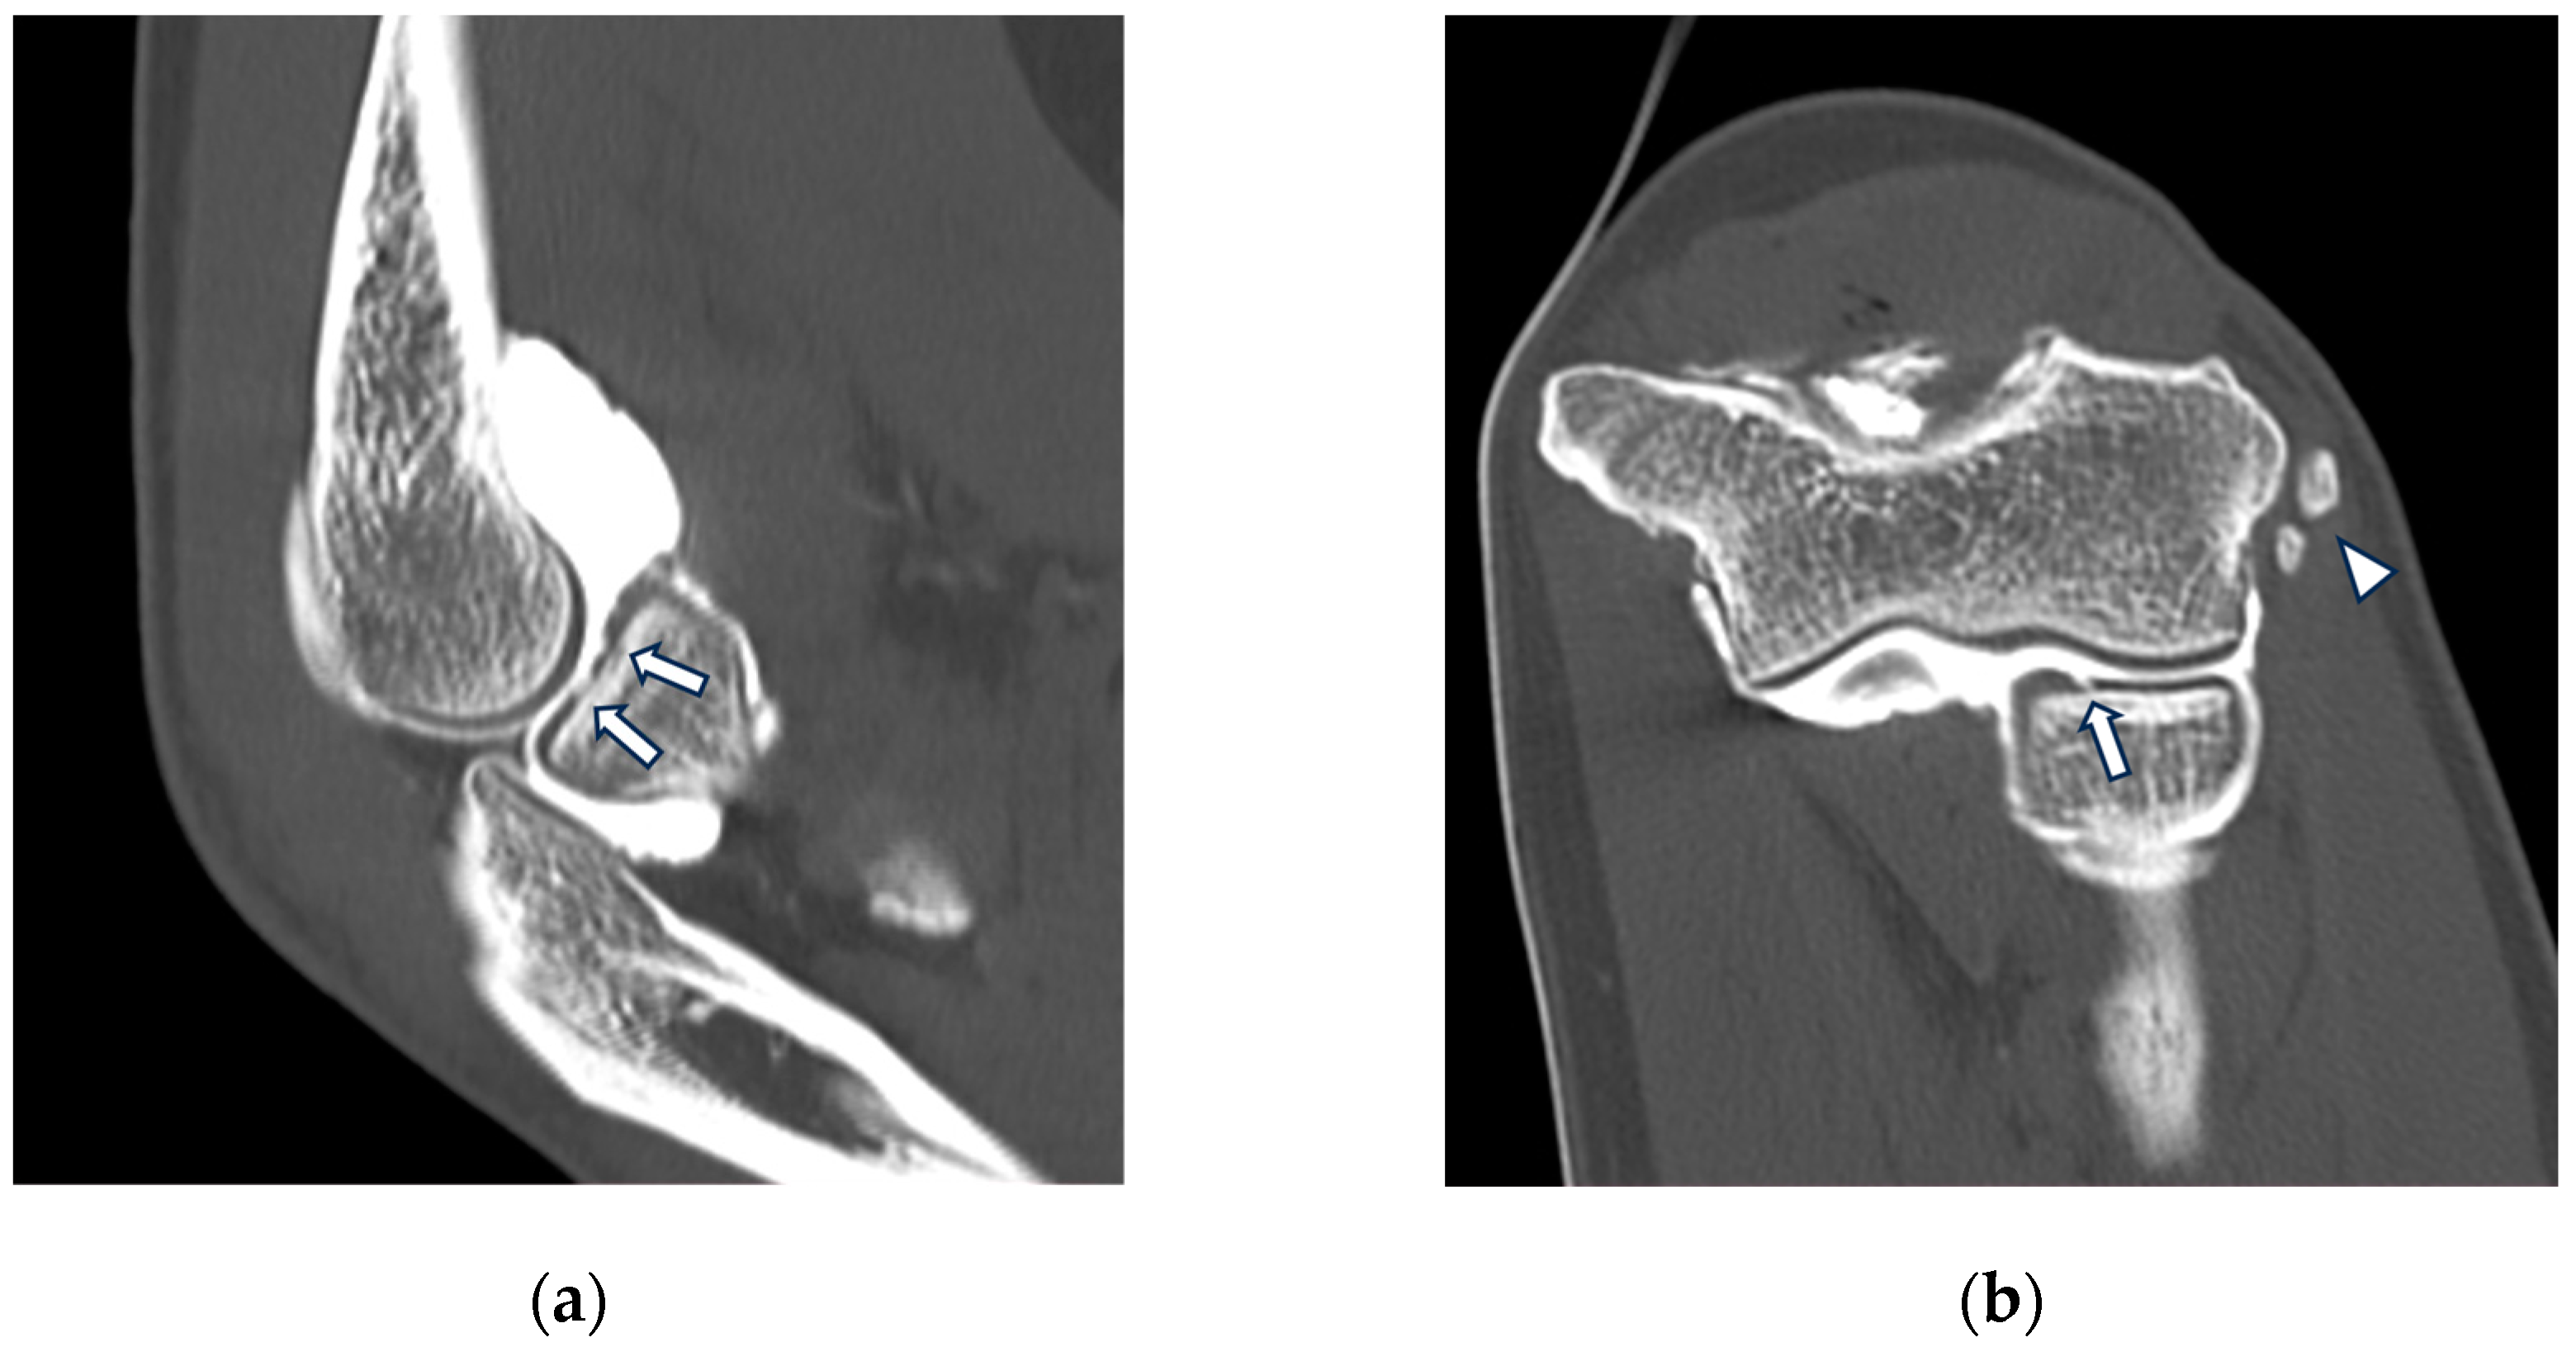

Figure 3.

CT arthrography of a patient with chronic elbow instability. (a) Sagittal image shows pitting and fissuring of radial head cartilage, involving >50% of its thickness (grade III) (white arrows); (b) coronal reformat of the same patient shows a focal full-thickness cartilage defect of the anteromedial radial head (grade IV) (white arrow). In the same image, mature calcifications can be seen at the insertion of the common extensor tendon (white arrowhead).

Loose bodies may result from osteochondritis dissecans (OCD), osteoarthritis, synovial chondromatosis (Figure 4), and osteochondral fractures. Even though elbow CT arthrography can detect loose bodies as small as 3 mm in diameter, plain radiography has been shown to have comparable sensitivity (84%) and specificity (71%). On the other hand, while plain radiography is a readily available first-level technique, it is often inaccurate: primary chondral lesions are not seen, it is difficult to distinguish between osteophytes and loose bodies and to determine whether the loose body is intra-articular [36]. The same study has shown CT arthrography to be more accurate than MR arthrography in determining loose body location, whether intra- or extra-articular [36]. OCD of the elbow typically affects the central and anterolateral aspect of the capitellum, most commonly related to repetitive valgus impaction injury of the radial head [37]. The development of OCD is thought to arise from a compromised vascular supply to the capitellum, leading to the fragmentation of osteochondral tissue and, ultimately, instability [38]. Instability of the osteochondral fragment can be assessed at CT arthrography by the visualization of a surrounding rim of intra-articular contrast [39]. Arthrographic examinations have a unique role to evaluate osteochondral injuries, being essential in determining the stability of such lesions. This determination is pivotal in deciding whether surgical intervention is necessary. OCD should be differentiated from Panner’s disease, a benign osteochondrosis of the capitellum that shows involvement of the whole epiphysis, does not result in loose body formation, and typically shows a subchondral vacuum phenomenon characterized by a crescent-shaped rim with air attenuation [40].

Figure 4.

CT-arthrography of a patient with rheumatoid arthritis. (a) Sagittal image shows pathological widening of the anterior humero-ulnar recess (asterisk), osteophytosis of the coronoid process (white arrowhead) and a distended posterior recess containing multiple non-calcific loose bodies compatible with secondary synovial chondromatosis (yellow arrowheads); (b) coronal image shows abnormal morphology and complete chondral erosion of both the radial head dish and lateral humeral condyle (yellow arrows).